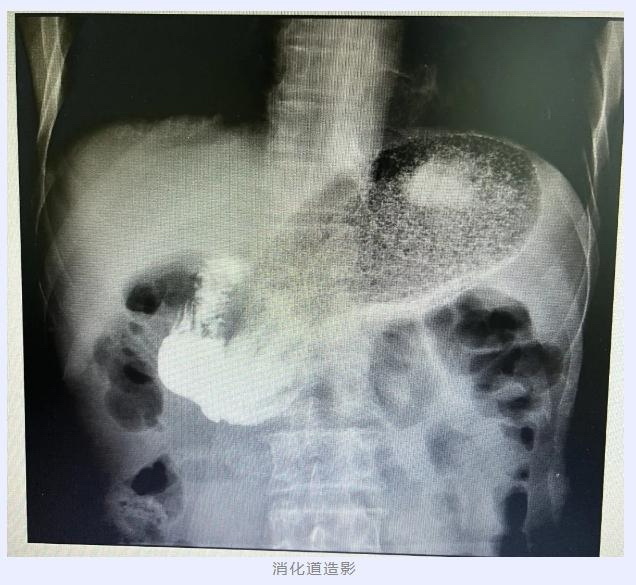

对于刘大爷迫切求助,翟博教授一方面耐心解答、安抚刘大爷焦虑的情绪,一方面安排刘大爷入院完善相关检查,经过胃镜、CT和消化道造影一系列检查后,翟博教授确定,刘大爷胃食管反流病的病因是:一个“扎不紧的口子”——食管裂孔疝。

找到了原因,翟博教授随即为刘大爷安排了手术治疗,拟定手术方案为“腹腔镜下食管裂孔疝修补术+胃底折叠术”。术中见胃底由扩大的食管裂孔疝入胸腔,还纳疝内容物后,关闭扩大的食管裂孔疝,为加强胃食管抗反流屏障作用,又以胃底包绕食管进行胃底折叠。